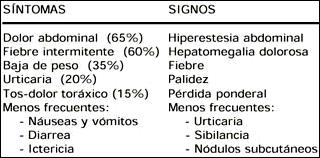

De las manifestaciones clínicas señaladas en la Tabla 2, los pacientes con infestación crónica generalmente cursan asintomáticos, con algunas excepciones como los niños quienes desarrollan síntomas de pancreatitis, mayor frecuencia de dolor abdominal y fiebre que en adultos o presencia de fiebre de origen desconocido que ocurre con o sin un curso obvio con o sin eosinofilia, o síntomas de cólico biliar debido a colangitis ascendente (3,10-13,12,14,15).

Tabla 2. Manifestaciones clínicas por fasciolosis

Estas manifestaciones pueden aparecer, dependiendo del número de metacercarias ingeridas, desde algunos dias hasta 2-3 meses después. La forma aguda dura 1-3 meses. La fiebre puede ser remitente, intermitente o irregular a predominio vespertino y alcanzar 40-42 °C. El dolor abdominal, de leve a severo, en hipocondrio derecho o subxifoideo a veces generalizado se acompaña de hiporexia, flatulencia, nauseas, vómitos y diarrea como los que presentó la paciente en discusión. La urticaria distingue la fase aguda de la crónica y puede acompañarse de broncoespasmo. La hepatomegalia puede llegar a la fosa iliaca derecha con incremento de su sensibilidad. La esplenomegalia no es común pero ha sido reportada. La ascitis cuando está presente constituye la respuesta inflamatoria a la penetración de la pared intestinal y de la cápsula de Glisson con irritación peritoneal correspondiente, pero no traduce falla hepática. La anemia es variable y la ictericia es muy infrecuente siendo mas leve que en la fase crónica. Los síntomas torácicos incluyen los rales húmedos o secos, pero también podría instalarse efusión pleural, neumotórax o pioneumotórax (3,7,10,11).

Algunas series señalan la existencia de una fase latente que dura meses o años, generalmente sin síntomas. La proporción de asintomáticos alcanza al 50% de los casos, pero ciertamente está subestimada, ya que éstos son detectados durante pruebas de tamizaje en los familiares de un caso diagnosticado (3,10).